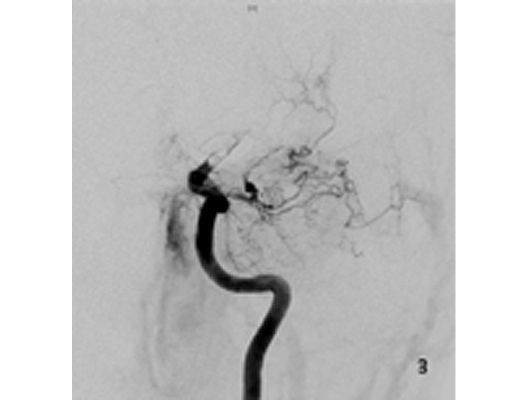

Angiographie: Rekanalisierende Verfahren

Rekanalisierende Verfahren (Wiedereröffnung von Blutgefäßen)

Mit den modernen Verfahren zur Wiedereröffnung von verschlossenen Blutgefäßen können wir Patienten mit Schlaganfall in vielen Fällen helfen. Das folgende Beispiel zeigt die angiographischen Bilder eines Patienten, der mit vollständiger Lähmung der rechten Körperhälfte und einer schweren Sprachstörung eingeliefert wurde. Ursächlich zeigte sich ein Verschluss der linken Halsschlagader, vermutlich auf dem Boden einer arteriosklerotischen Einengung (Bild 1). Das Gefäß wurde daraufhin mit einem Stent wiedereröffnet (Bild 2). Zusätzlich zeigte sich ein Verschluss der Endstrecke des Gefäßes durch Blutgerinnsel (Bild 3). Diese konnten vollständig entfernt werden (Bild 4). Der Patient erholte sich nach der Behandlung innerhalb weniger Tage vollständig.